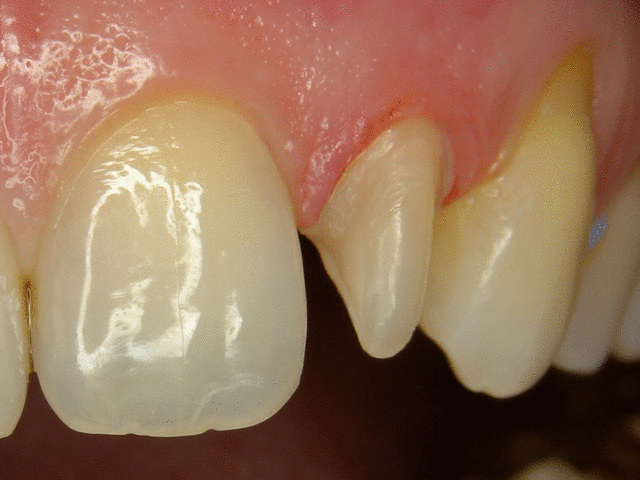

Tient, un petit cas de facettes sur les incisives du bas pour changer du haut...cas de décoloration, résistant au blanchiment...c'était pas mon apn...je testais un Canon 50D, 100mm canon, flash Mr-14X...pas mal.

Bof, les tailles sont moches, ça va pas coller, besoin de 5 ou 6 endo, puis des implants...

+1 photo manque de couleur, mais c'était un test avec le 50D, fait rapido, de plus, la compression utilisé est moche (passer de 8 mp à 275k )

Personne ne râle contre mes tailles ?

J'aime mieux mon 450D